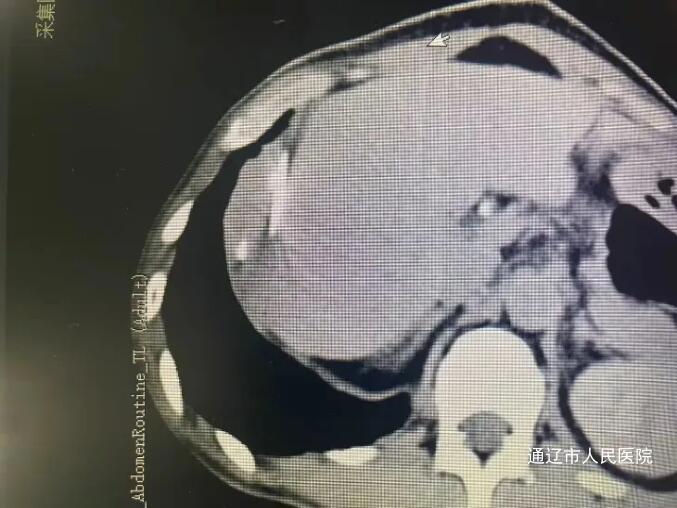

近日,我院肝胆胰外科成功实施了全市首例CT引导下肝肿瘤纳米刀消融术,标志着我院肝胆胰外科在肿瘤微创消融领域迈上新台阶,填补了本地区医疗技术空白。该患者男性,因腹胀于我院就诊,完善相关检查诊断结肠癌伴肠梗阻,肝占位性病变考虑转移瘤,讨论病情后决定一期行腹腔镜下根治性右半结肠切除术,术后复查腹部增强CT、增强肝脏MRI提示肝脏转移瘤有进展趋势,遂行CT引导下肝肿瘤纳米刀消融术。

手术过程中,患者行全身麻醉,在解放军总医院肖越勇教授指导下,我院肝胆胰外科主任医师郭雅明、手术麻醉科副主任医师高飞、CT室医护团队在CT引导下确认病灶位置并进针,确保电极区域完全包裹肿瘤后开始消融。消融过程中电流上升反馈良好,术后即刻增强CT显示消融范围覆盖病灶,周围血管、胆道结构完好无损伤,出现明显气体影,消融效果良好。消融完成后,退出穿刺针,手术顺利结束,术中麻醉效果满意,生命体征平稳,麻醉恢复后无腹痛腹胀,恶心呕吐等不适。术后给予对症支持治疗,患者恢复良好。和传统的消融治疗方式不同,纳米刀消融技术是通过脉冲电场导致细胞不可逆电穿孔,从而实现肿瘤组织杀伤,是一种非热选择性物理消融技术,可在实现消融肿瘤的同时,保留肿瘤周围的重要管道结构(血管、胆管和神经)完整性,并且无热沉效应,消融肿瘤细胞,适用于消融治疗靠近肝门、胆囊、膈肌和结肠等肝脏特殊部位的肿瘤有着独特的优势。纳米刀消融手术为现阶段先进、安全的肿瘤消融技术,它为无法使用传统手术方式的特殊部位癌症患者提供了新的治疗方式,还具有能够选择性消融,时间短、创口小等优点,一定程度上能够改善生活质量,延长生存时间,纳米刀消融对不能手术的肝癌、肺癌特别是胰腺癌具备较大的技术优势。此次全市首例纳米刀消融术的开展,标志我院微创介入技术取得重大突破,也为疑难肿瘤患者提供了更为先进技术的诊疗手段。